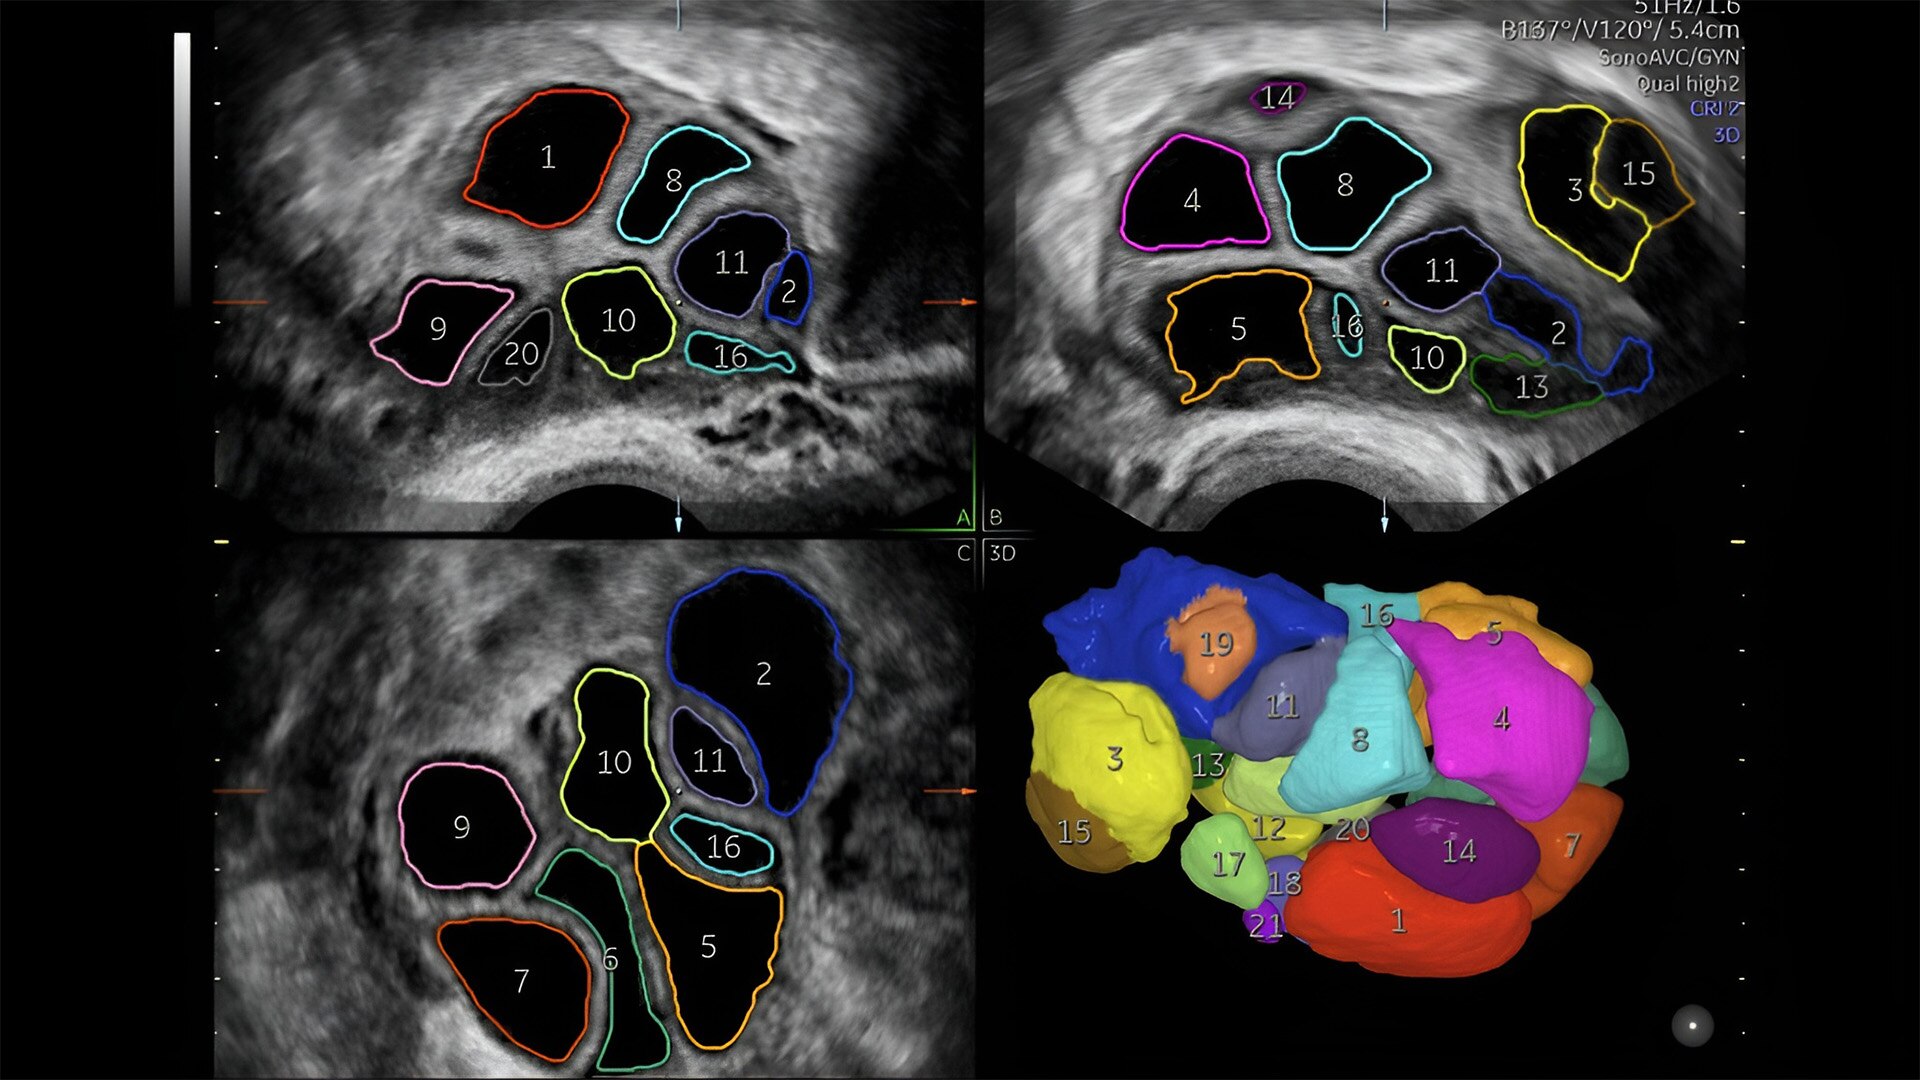

Fetal heart assessment

Detect, diagnose, and monitor with confidence using Radiant and fetalHQ

Fetal heart evaluation

Get to the heart of the matter

Identifying fetal cardiac abnormalities earlier means you can intervene sooner, plan for delivery, and potentially improve outcomes. The Voluson Expert 22 provides a full solution of progressive tools, to help distinguish the tiniest structures with stunning clarity to provide patient answers faster.